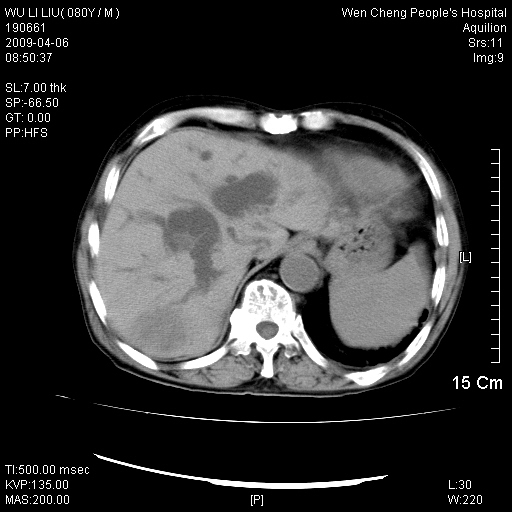

以下是引用zjzjr在2009-4-7 12:13:00的发言:[br]支持多发性转移瘤,右股骨颈骨折,腰椎亦有压缩性骨折.肝内胆管结石伴胆内外胆管扩张,左肾结石.

以下是引用liaoqiang在2009-4-7 8:44:00的发言:[br]考虑多发性骨髓瘤伴肝肺转移、肝内胆管结石、左肾结石、右股骨颈骨折。

以下是引用余辉在2009-4-7 8:52:00的发言:[br]椎骨及骨盆骨质疏松,骨破坏主要累及椎体,各骨破坏较广泛,各病灶边缘均较清晰锐利,血沉增快,白细胞增高.支持考虑多发骨髓瘤,建议查本尿周氏蛋白.[br]胆内胆管及左肾结石[br]右股骨颈骨折,考虑病理性